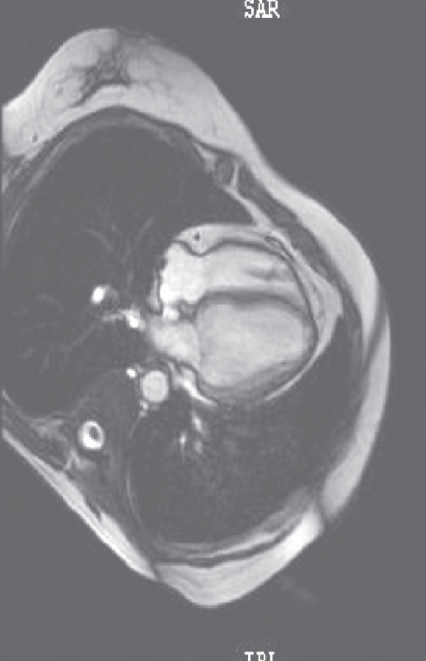

心脏MRI见心肌灌注均匀(图4)。

图4 心肌MRI结果